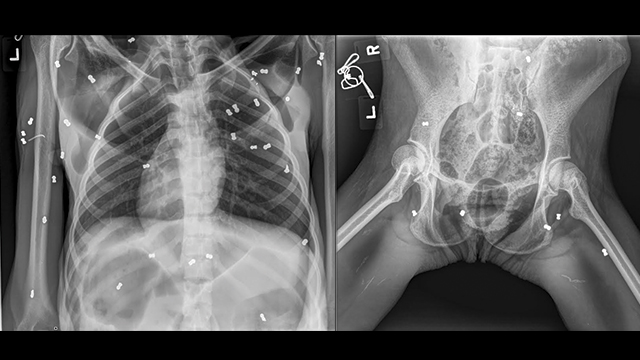

Hasil X-Ray pada Hope memperlihatkan lokasi peluru senapan angin yang ditembakkan ke tubuh satwa malang ini. Foto: Foto: Yayasan Ekonomi Lestari-Sumatran Orangutan Conservation Programme (YEL-SOCP)

Selain itu, hasil pemeriksaan dengan X-ray menunjukkan sebanyak 74 butir peluru senapan angin tersebar di seluruh badan, patah tulang Clavicula kiri terbuka (tulang mencuat keluar dari kulit), retak tulang pelvis kiri dengan keretakan kurang lebih 2 cm.